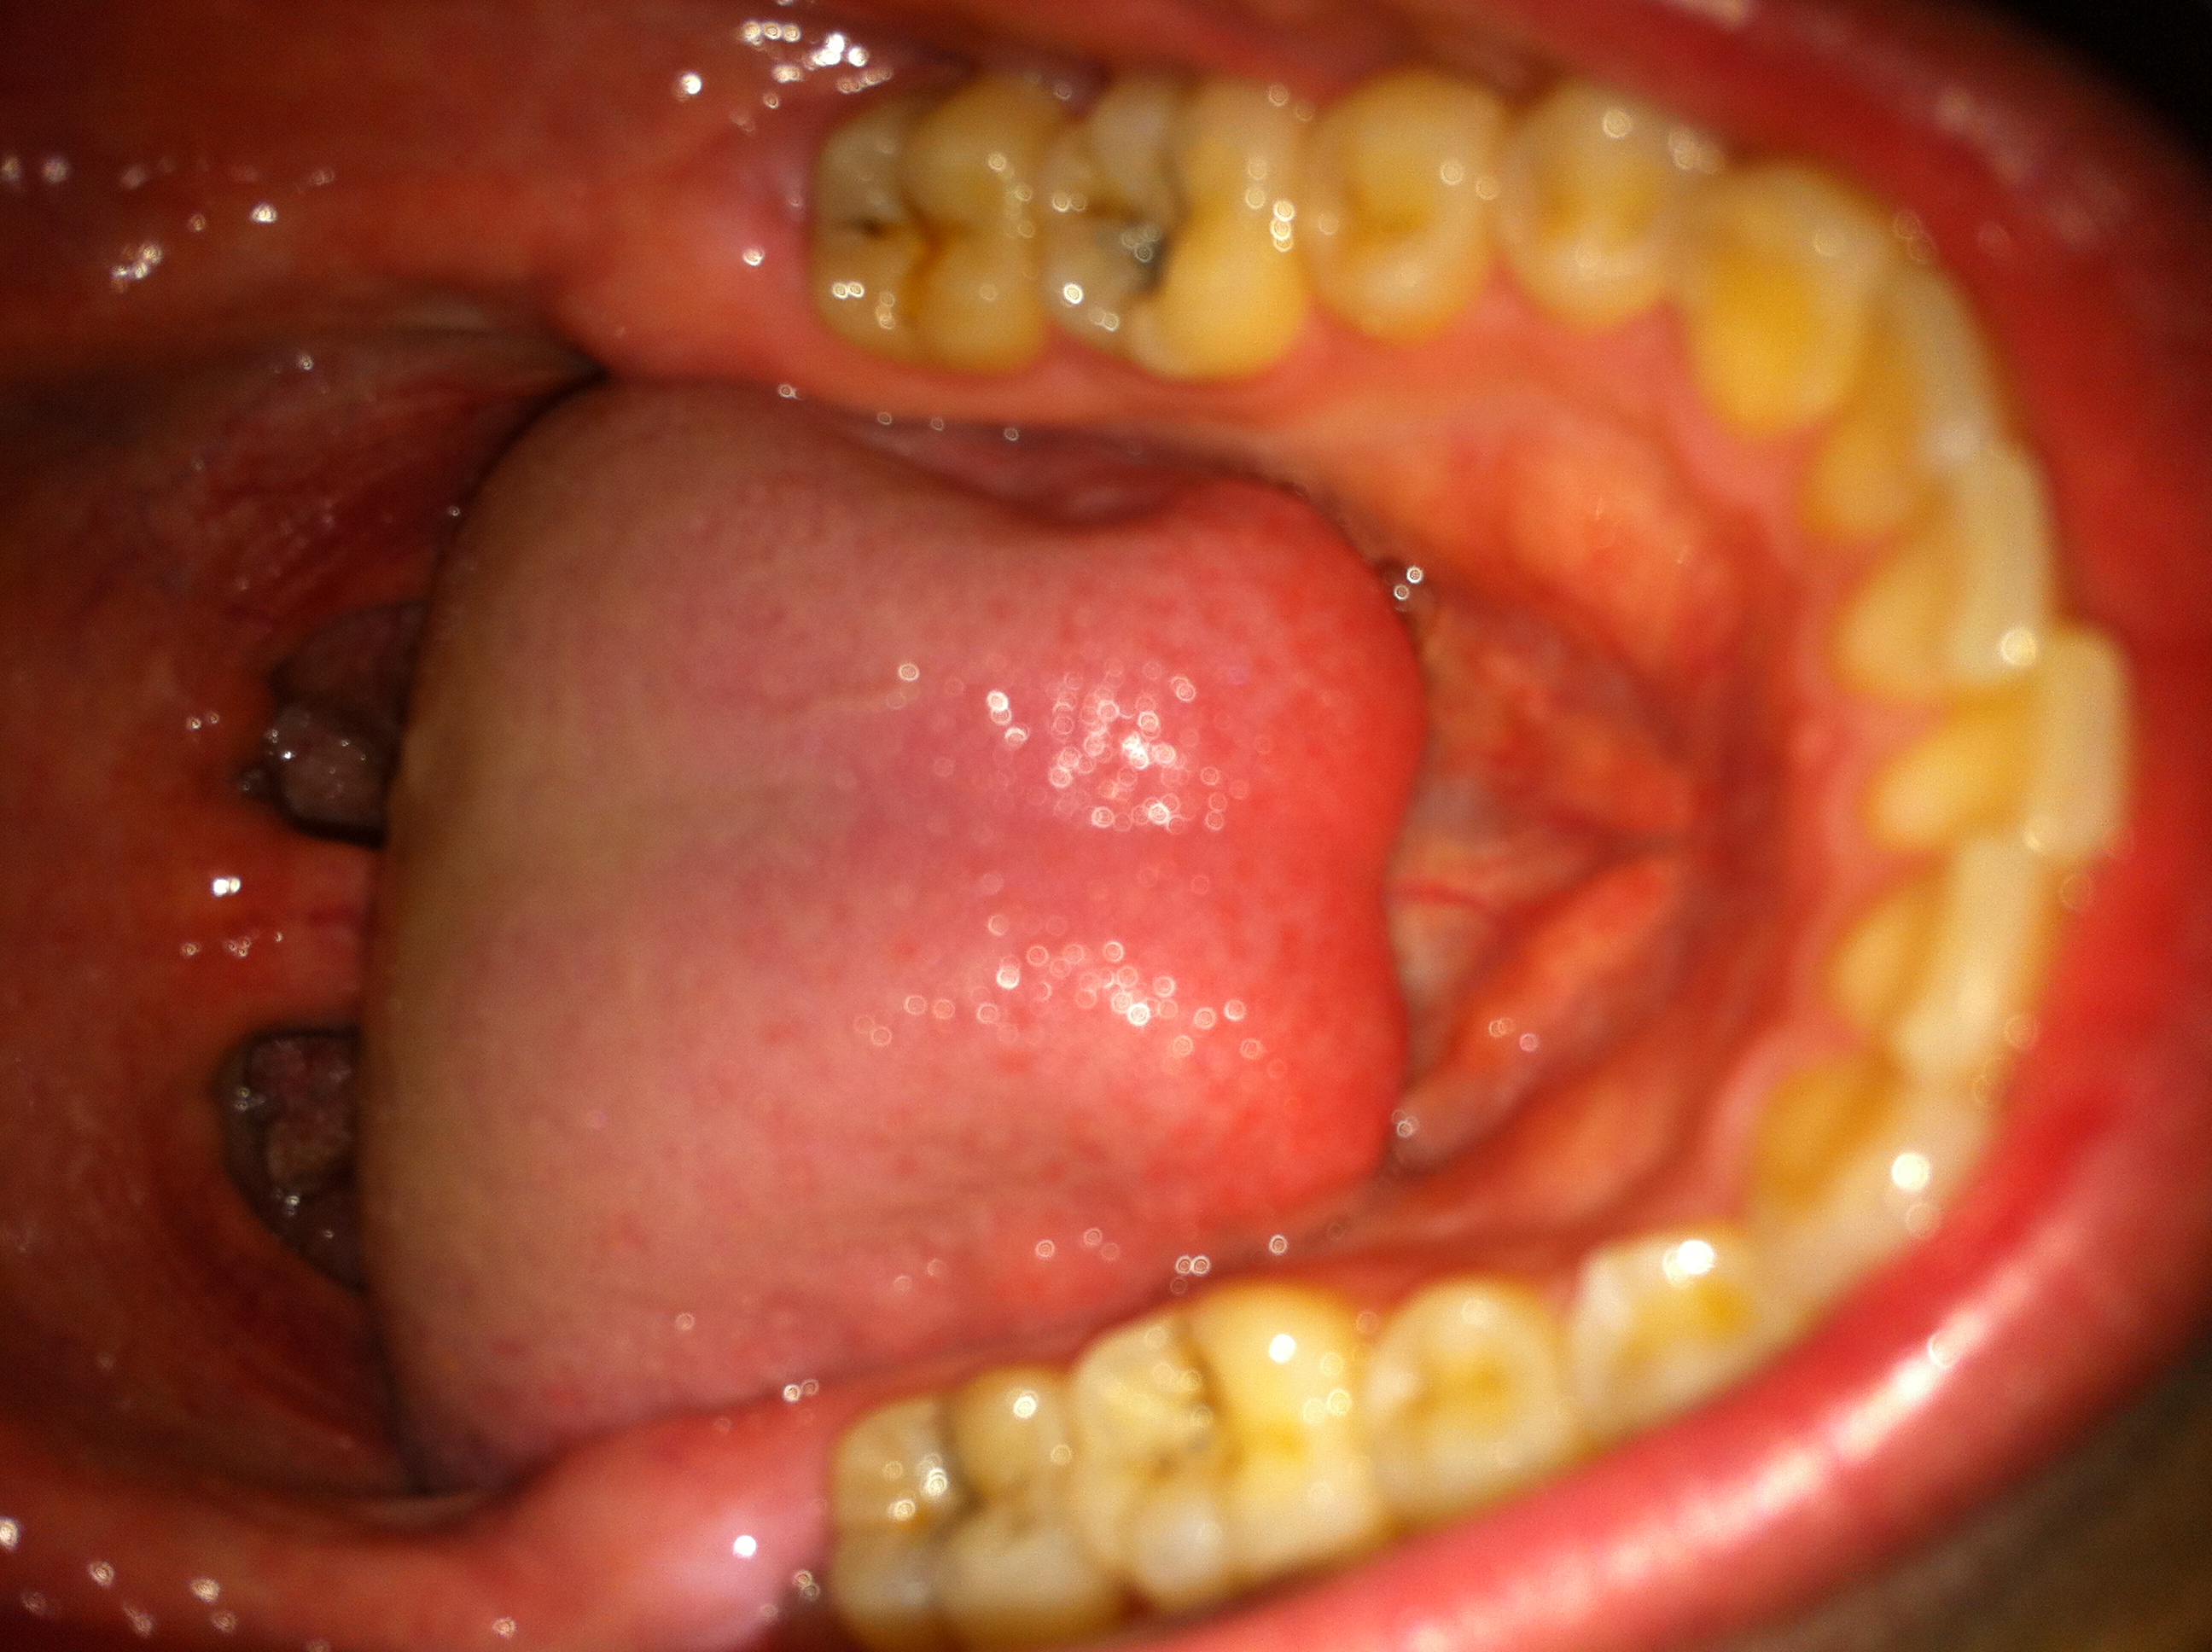

ik zie zojuist dat mijn verstandskies doorkomt. moet ik nu de tandarts bellen voor een afspraak om hem te laten trekken ivm ruimtegebrek? op de foto zie je dat er een ondertand scheef staat. wordt dit erger door de kostt van mijn verstandskiezen? is het misschien een idee om mijn beide grote kiezen te laten trekken omdat ze slecht zijn en me verstandkiezen onder door te laten groeien? dit moet dan wel snel gebeuren omdat ik nu nog geen 18 ben dan is het goedkoper. alvast bedankt!

Ik vind trouwens de ruimte helemaal niet zo beperkt. In dit geval en met jouw leeftijd zou ik ze rustig laten doorkomen, als dat binnen een jaar niet lukt kan je altijd nog besluiten ze te laten verwijderen. Nu is er nog geen echte aanleiding.